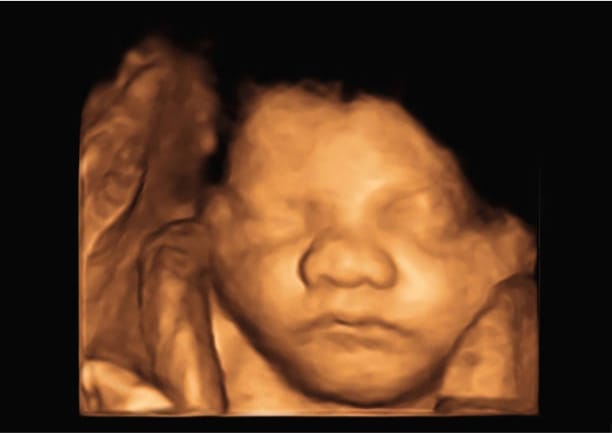

3D Ultrasounds

3D ultrasounds are a step up in the visual experience, offering a three-dimensional image, giving depth to the baby’s features.

These images allow a detailed view of the baby’s external appearance, including facial features.

A 3D ultrasound provides a clearer picture of the fetus’ external anatomy, aiding in diagnosing certain physical abnormalities, such as cleft lip or spinal issues, which might not be as clearly visible on a 2D scan.

However, it’s important to note that 3D ultrasounds are not a replacement for 2D scans but rather a complementary tool in certain diagnostic contexts.